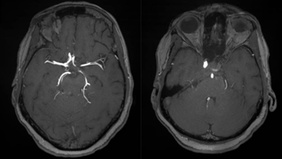

Endovascular Treatment Of Carotid Body Tumor With Embospheres

By Smit SHAH

Published on February 24, 2026